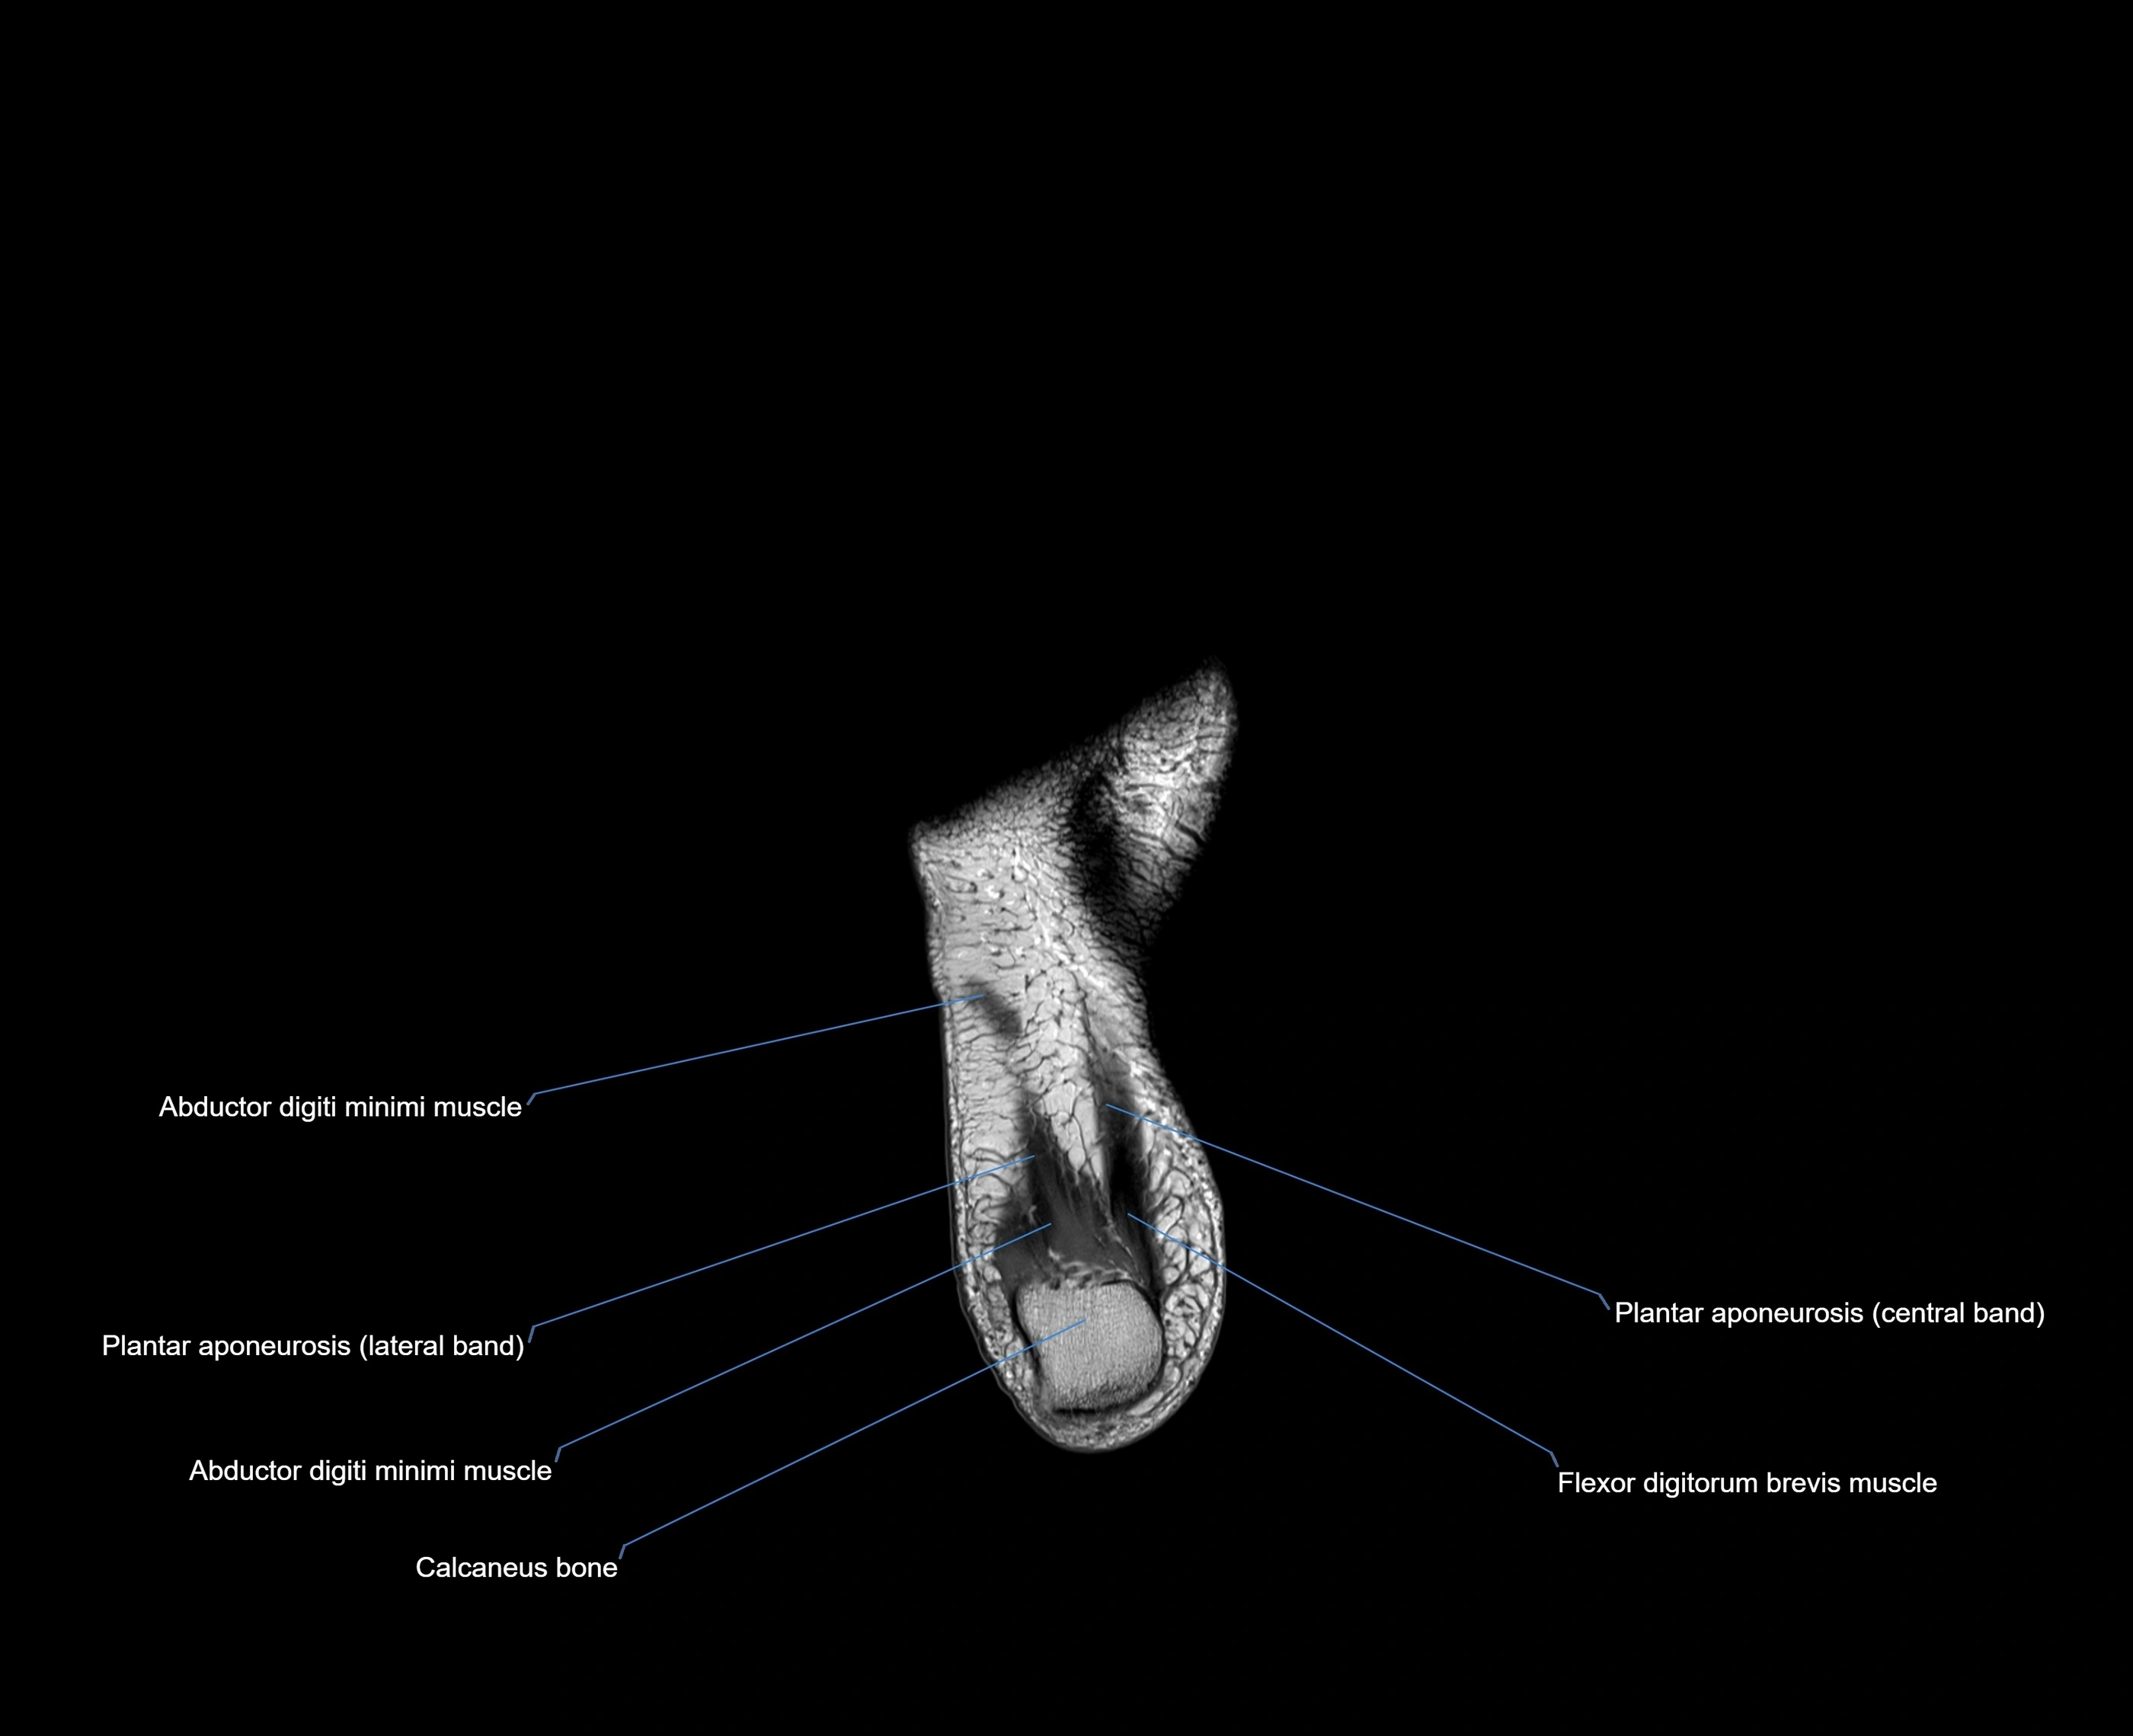

MRI image